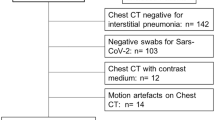

In order to select chest CT scans for analysis, our exclusion criteria were RT-PCR for SARS-CoV-2 that was ultimately determined to be negative. Figure 1 shows the patient's enrollment flowchart.

Patient demographics, clinical and laboratory findings

Demographics, clinical and laboratory findings are reported in Table 1. The analysis included 98 patients (median age, 61 years old; range 23–91 years old), 39/98 (39.80%) were females. Five patients were excluded for negative result at RT-PCR test (Fig. 1). No symptoms (fever, cough, respiratory failure, dyspnea or other including arthralgia, diarrhea, leukopenia, nausea), no comorbidities (hypertension, diabetes, neurological, cardiovascular, oncological, pulmonary) determined differences statistically significant in terms of patient outcome (Table 1). Among admission laboratory findings, SpO2, high sensitivity C-reactive protein (HS CRP), leukocyte count, neutrophils percentage value, lactate dehydrogenase value (LDH), d-dimer, troponin, creatinine and azotemia, ALT, AST and bilirubin values showed differences statistically significant compared to patient outcome (Table 1). SpO2 was significantly lower in patients hospitalized in critical conditions or died while age, HS CRP, leukocyte count, neutrophils percentage value, LDH, d-dimer, troponin, creatinine and azotemia, ALT, AST and bilirubin values were significantly higher (Table 1).

Automatic segmentation on CT images based on Hounsfield unit was performed on 74 patients because the AI tool was not able to segment automatically GGO, consolidations or emphysema in 24/98 (24.5%) cases (Fig. 1). Therefore, radiological severity visual score on CT for COVID-19 disease was provided for these 74 patients.